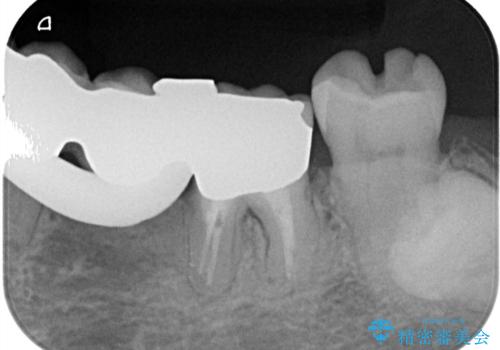

- 主訴:左下一番奥の銀の詰め物が外れてしまった。やり替えを機に綺麗なものを入れたい。

保険のメタルインレー脱離によるやり替え希望だったため、審美性・清掃性の良いセラミックインレーでのやり替えとなりました。

メタルインレー脱離後の窩洞をセラミックインレー窩洞に再形成し直し印象しています。遠心・舌側面のカリエスの除去、残存歯質の破折リスクを考えアンレー形態となりました。

アンレー装着時にはラバーダム防湿を行っています。